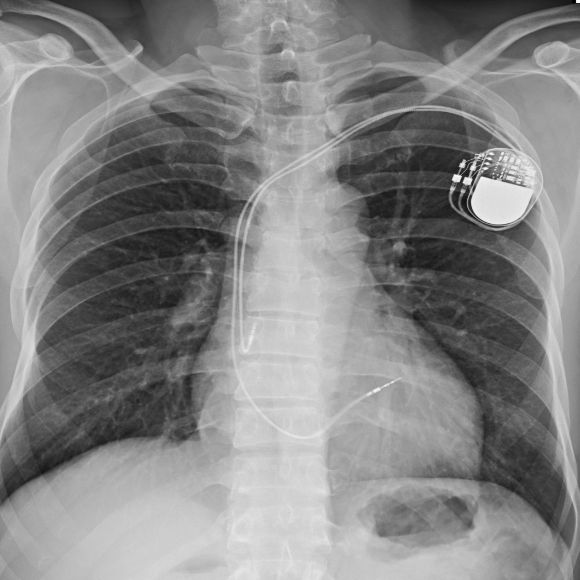

Ein Herzschrittmacher ist ein kleines elektronisches Gerät, das elektrische Impulse an das Herz sendet, wenn der natürliche Herzschlag zu langsam (Bradykadie) oder unregelmäßig ist (Arrhythmie). Er hilft also, den Herzrhythmus zu stabilisieren und typische Risiken von Herzrhythmusstörungen und Herzinsuffizienz zu vermeiden. Aber was ist der Unterschied zwischen einem ICD und einem Schrittmacher?

Herzschrittmacher gelten als sichere und zuverlässige Geräte. Sie bestehen aus einer Batterie und der Steuerungselektronik in einem Gehäuse und halten in der Regel 5 bis 10 Jahre.

Herzschrittmacher werden standardmäßig in Krankenhäusern implantiert. Der Eingriff dauert etwa eine Stunde und ist dank örtlicher Betäubung weitgehend schmerzfrei. Danach wird das Gerät individuell programmiert und die Elektronik wird auf Ihre Herzsituation angepasst.

Der Eingriff erfolgt meist unter örtlicher Betäubung. Über eine Vene werden Elektroden ins Herz eingeführt und mit dem Schrittmacher verbunden, der unter der Haut im Brustbereich eingesetzt wird. Die Operation dauert in der Regel eine Stunde und gilt als risikoarm.

Ein Herzschrittmacher verlängert die Lebenserwartung deutlich, da er Herzrhythmusstörungen zuverlässig ausgleicht. Die Lebenserwartung entspricht bei ansonsten guter Gesundheit oft der von Menschen ohne Schrittmacher. Das Gerät selbst hält je nach Modell und Nutzung etwa bis zu 10 Jahre. Danach ist ein Austausch im Rahmen eines kleinen operativen Eingriffs möglich.